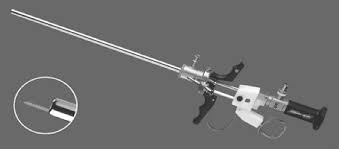

Nefroscopio

Telescopio Panoview con ocular desplazado lateralmente, dirección de visión de 12° y canal de trabajo de 6 Fr.